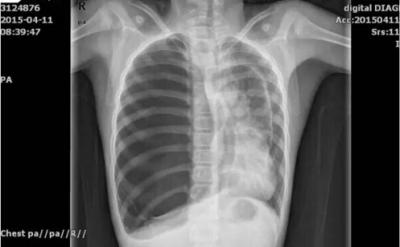

9岁的鹏鹏是瓯海人,前阵子,鹏鹏连续咳嗽,家人带他到温医大附二院就诊。医生给鹏鹏检查时发现他的气管明显往左偏,右肺听不到呼吸音。在X光片上,医生惊讶地发现鹏鹏居然“没有”右肺。医生又为鹏鹏进行了CT检查,同样没有发现右肺。

医生当时考虑鹏鹏是先天性的肺发育不良,但增强CT检查结果却出乎意料:孩子右侧三分之二胸腔被一个巨型的肺大疱所占据,右侧肺部被挤压在胸腔的一角。这就是做CT的时候,看不到鹏鹏右侧肺部的原因——巨型的肺大疱遮住了肺部。“鹏鹏得的是典型的‘消失肺综合征’。这种病十分罕见而且以往多见于青年男性,这一次竟然发生在一个9岁小男孩的身上!”温医大附二院儿童心胸外科副主任赵琦峰说。